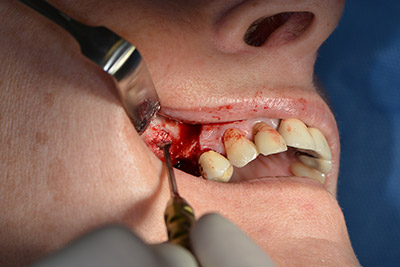

The classic incision (crestal, buccal relief) and the preparation of the mucoperiosteal flap enabled a good overview.

Sky implants (bredent) were used this case. The surgical protocol of these, specify pilot drilling at about 1200 rpm (Fig. 9).